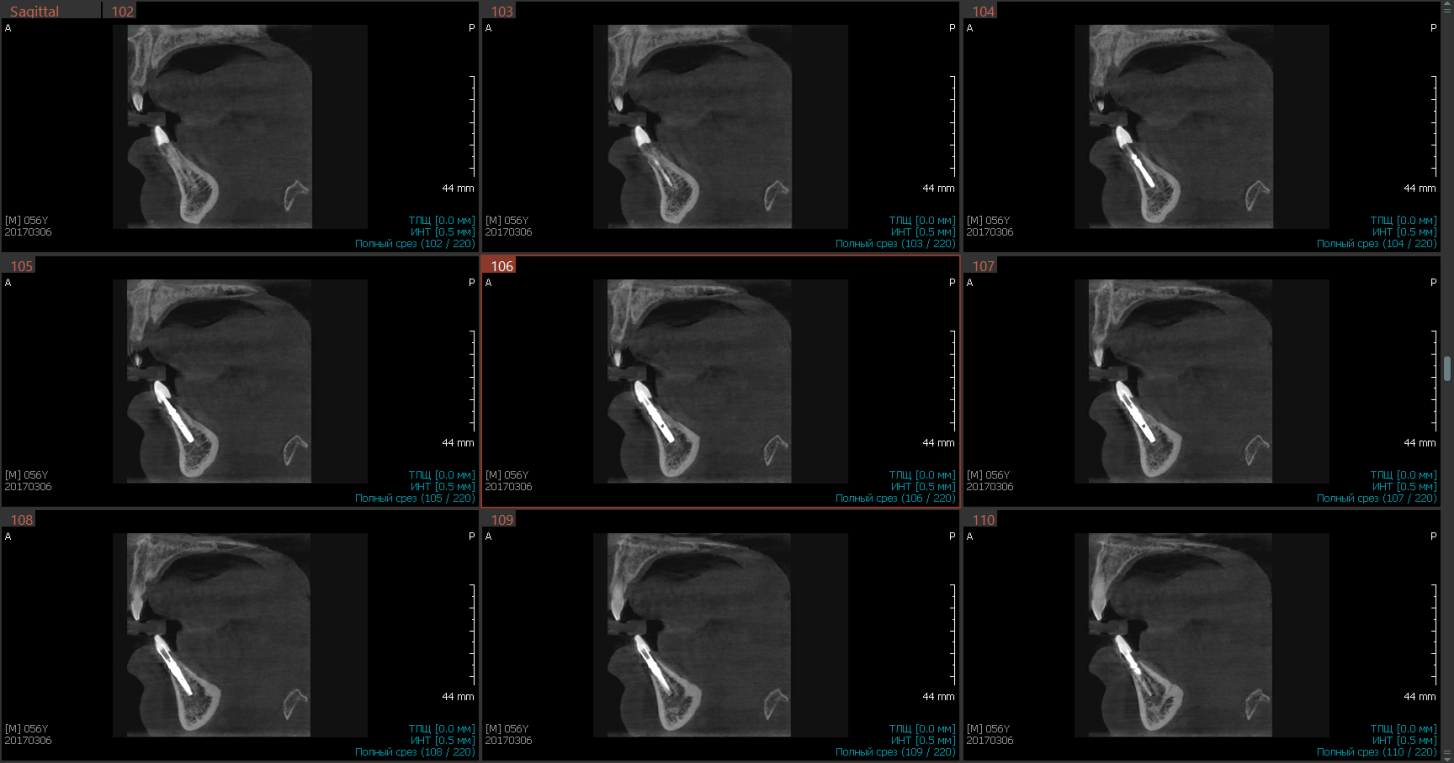

Рис.2 Кросс-секции для выявления градуса наклона имплантатов в области 31,41 зубов при первичной стабильности. Инклинация имплантатов корректна

Следует выделить кросс-секции, которые обеспечивают полную ясность при анализе, как моделирования виртуального имплантата, так и проверки корректности его установки, выделяя важные показатели клинического случая: торка и наклона, визуализация качества эндодонтического лечения соседних зубов.